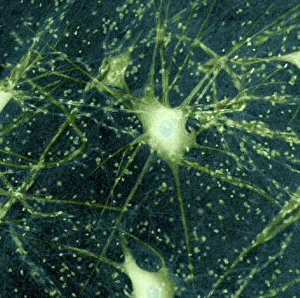

The central nervous system, the intricate network that governs our every thought and movement, is a marvel of complexity. From the delicate cerebellum tissue to the detailed light micrograph capturing its essence, we are reminded of its importance in maintaining balance and coordination. Anatomy comes alive as we explore the human brain from an inferior view. The intricacy of brain fibers is revealed through DTI MRI scans like C017/7099 and C017/7035, showcasing their vital role in transmitting information throughout this extraordinary organ. Artistic renderings bring us closer to understanding the medulla oblongata's significance within the brain. Its portrayal in various artworks allows us to appreciate how it controls essential functions such as breathing and heart rate. As we delve deeper into studying the central nervous system, models of the human brain provide invaluable insights into its structure and organization. Lateral views reveal countless regions responsible for cognition, emotion regulation, sensory perception, and motor control. Microscope slides offer glimpses into nerve cells' intricate architecture—a testament to their ability to transmit electrical signals at lightning speed. Meanwhile, glial stem cell cultures captured under a light microscope remind us of their crucial role in supporting neuronal function. Finally, artistic representations unveil the limbic system's enigmatic nature—an interconnected web responsible for emotions and memory formation. These captivating artworks allow us to visualize this complex network within our brains. Exploring these hints provides a glimpse into the awe-inspiring world of our central nervous system—the very foundation upon which our thoughts, actions, memories reside—reminding us just how remarkable our brains truly are.